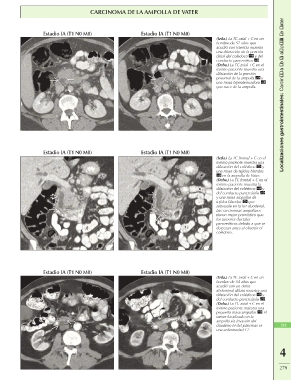

CARCINOMA DE LA AMPOLLA DE VATER

Estadio IA (T1 N0 M0) Estadio IA (T1 N0 M0) (Izda.) La TC axial + C en un Localizaciones gastrointestinales: Carcinoma de la ampolla de Vater

hombre de 57 años que

acudió con ictericia muestra

una dilatación de la porción

distal del colédoco y del

conducto pancreático .

(Dcha.) La TC axial + C en el

mismo paciente muestra una

dilatación de la porción

proximal de la ampolla y

una masa hipoatenuadora

que nace de la ampolla.

Estadio IA (T1 N0 M0) Estadio IA (T1 N0 M0)

(Izda.) La TC frontal + C en el

dilatación del colédoco y

una masa de tejidos blandos

en la ampolla de Vater.

(Dcha.) La TC frontal + C en el

mismo paciente muestra la

del conducto pancreático

y una masa ampollar de

tejidos blandos que

sobresale en la luz duodenal.

Los carcinomas ampollares

tienen mejor pronóstico que

los tumores ductales

pancreáticos debido a que se

detectan antes al obstruir el

colédoco.

Estadio IA (T1 N0 M0) (Izda.) La TC axial + C en un

hombre de 54 años que

acudió con un dolor 519

abdominal difuso muestra una

del conducto pancreático .

pequeña masa ampollar . El

tumor localizado en la

ampolla sin invasión del

duodeno ni del páncreas es

una enfermedad T1.